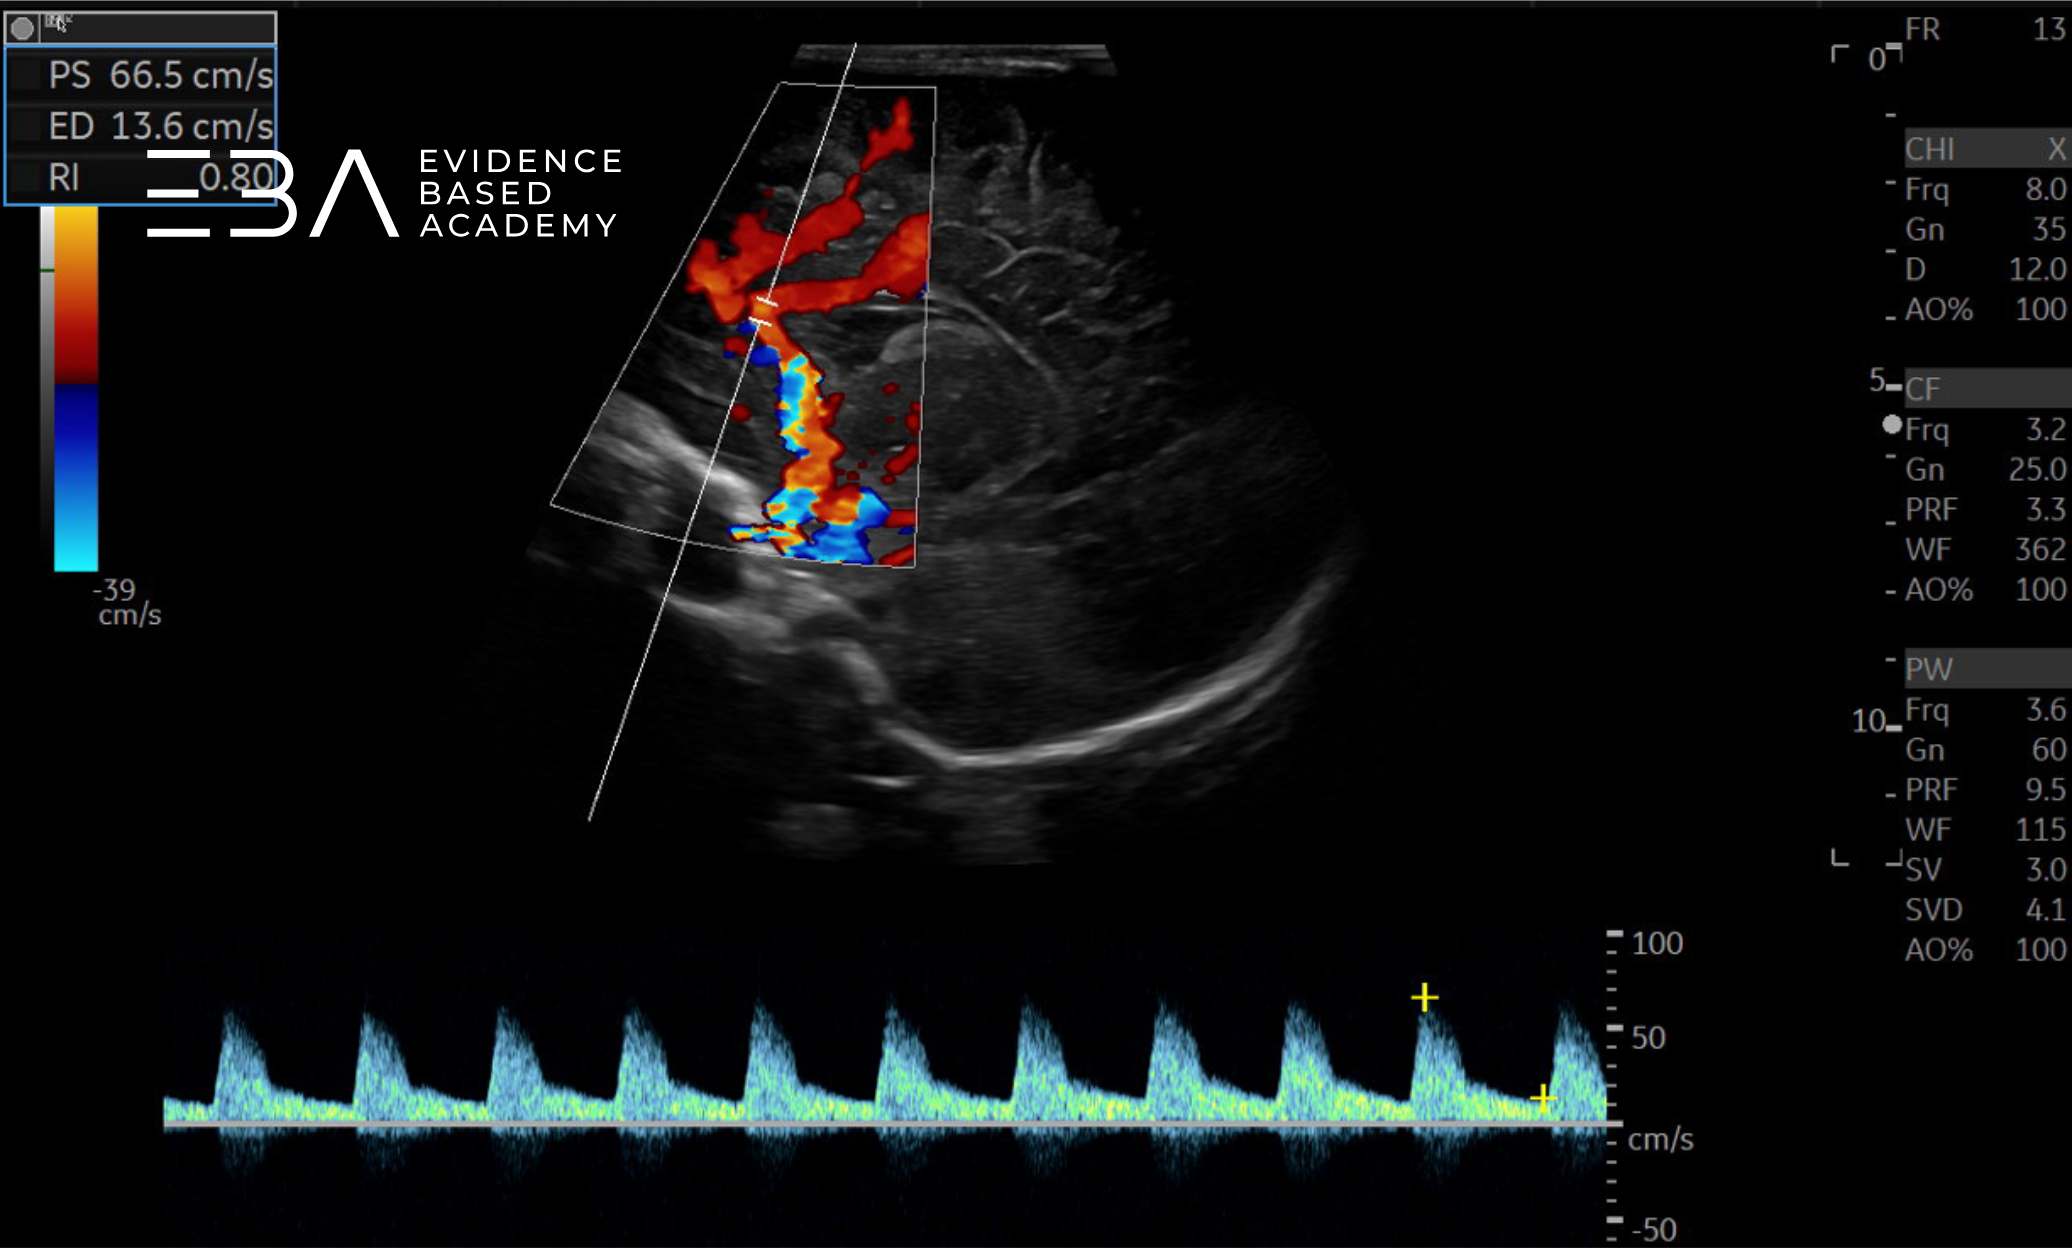

Wskaźnik oporu

Wskaźnik oporu (resistive index, RI) definiowany jest wzorem: RI = (PSV – EDV) / PSV, gdzie PSV oznacza szczytową prędkość skurczową, a EDV – prędkość końcoworozkurczową (3, 5, 6). Wskaźnik RI jest niezależny od kąta padania wiązki ultradźwiękowej, w przeciwieństwie do wartości bezwzględnych prędkości (3).

Na wartość RI wpływa wiele czynników, w tym prędkość przepływu, objętość krwi, obecność wrodzonych wad serca i opór naczyniowy obwodowy (5). Prawidłowy RI stopniowo obniża się z wiekiem (6). Prawidłowe wartości RI w zależności od wieku to (6):

• wcześniak: RI = 0,77

• noworodek donoszony: RI = 0,65-0,75

RI mierzymy zazwyczaj w tętnicy przedniej mózgu (anterior cerebral artery, ACA), poniżej kolana ciała modzelowatego, w projekcji strzałkowej pośrodkowej (3).

Wartości RI mają znaczenie kliniczne jako wskaźnik zaburzeń hemodynamicznych. RI >0,85 sugeruje niski przepływ rozkurczowy (np. w przebiegu obrzęku mózgu lub podwyższonego ciśnienia wewnątrzczaszkowego), natomiast RI <0,55 – wysoki przepływ rozkurczowy (np. w reperfuzji po niedotlenieniu) (8).

zdj. f

Przepływ krwi w tętnicy przedniej mózgu.

Pomiar wskaźnika oporu w tętnicy przedniej mózgu.